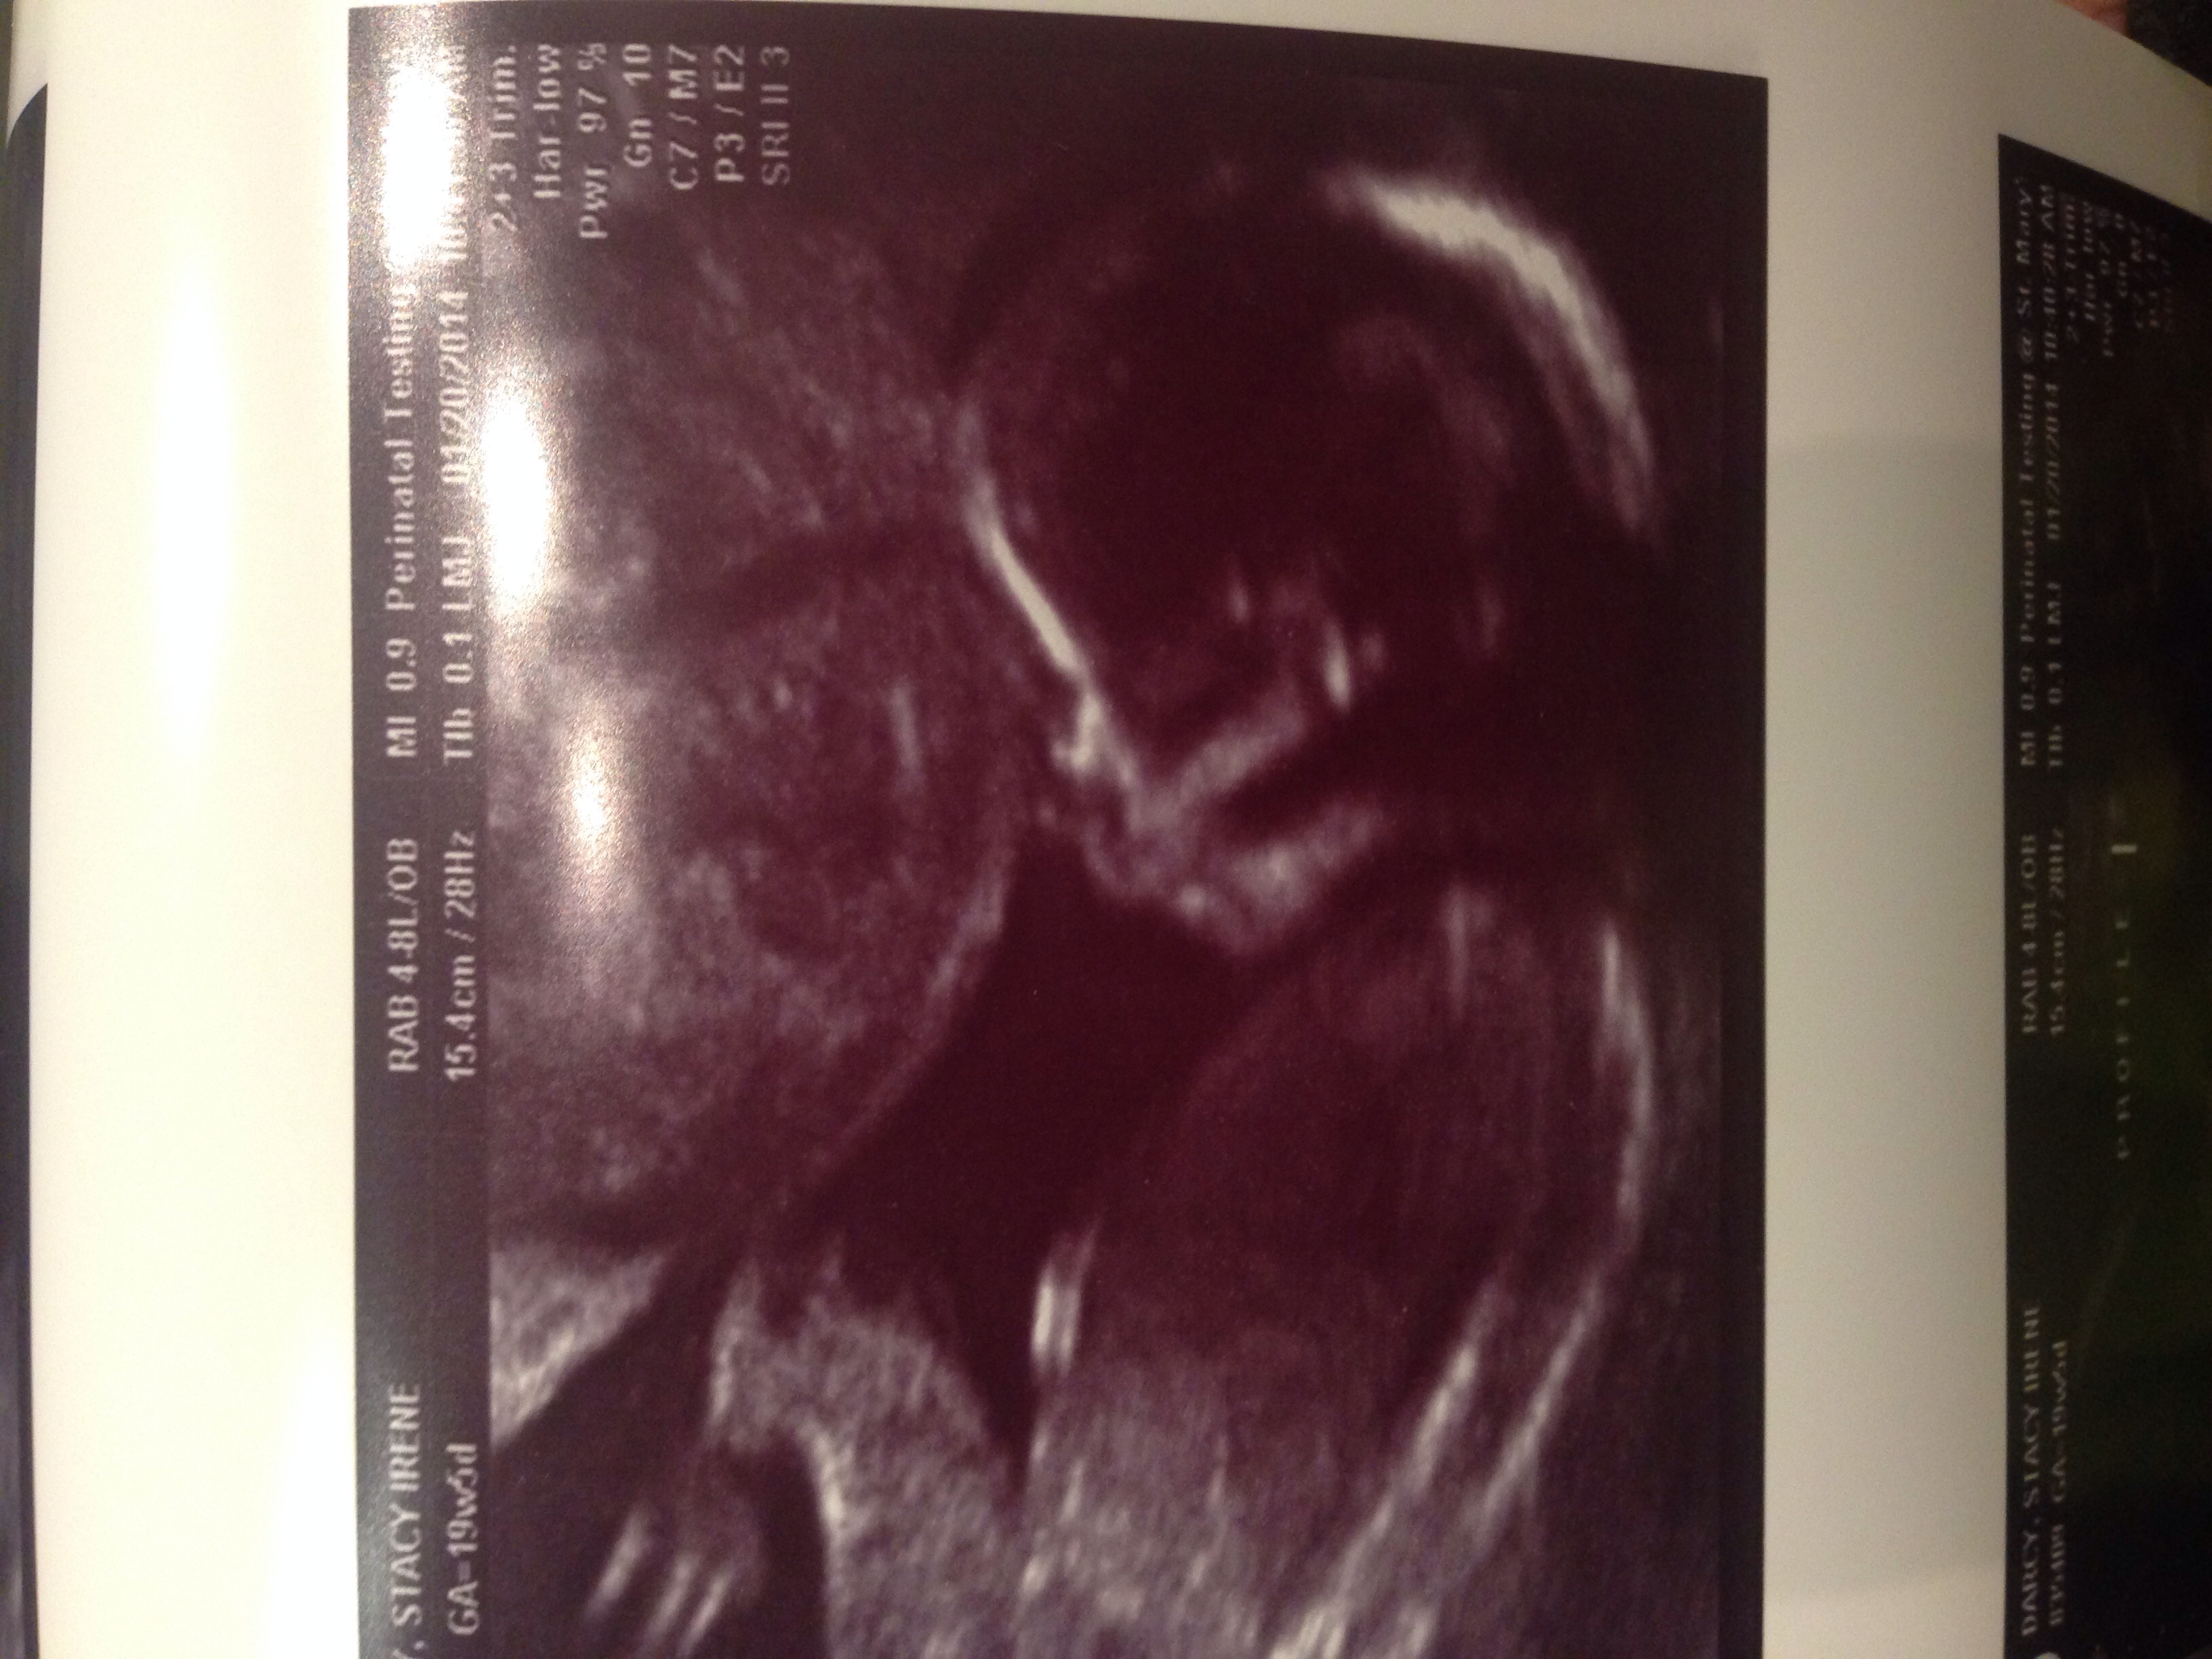

I'm late posting, but we found out we are having a boy yesterday. We didnt expect our doc to guve us a 3D shot, but he did :) My 8yr old son could not be more excited to have a brother on the way. We are due June 17. :). Congrats to all the mommies out there!!!